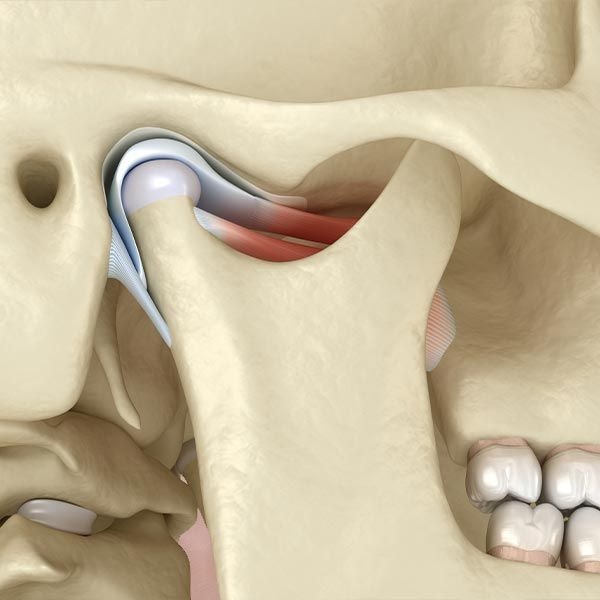

Don't Let Facial Pain Turn Into Something Worse

Facial pain and discomfort can often be a sign of a more serious oral health issue, and the condition will only worsen if left untreated. Dr. Anderson uses state-of-the-art technology to precisely diagnose your facial pain and create a custom treatment plan. He is experienced in diagnosing and treating a variety of issues before they can cause further damage to your teeth, gums, and jawbone.

Through oral surgery, Dr. Anderson can alleviate your pain and restore your oral health so you can maintain lasting and beneficial results.